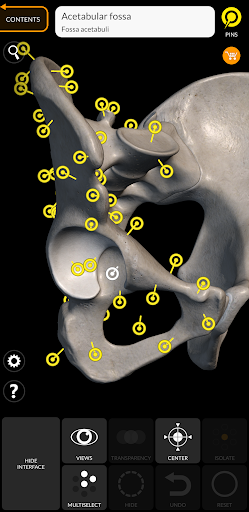

Mỗi xương của bộ xương người đã được tái tạo ở dạng 3D, bạn có thể xoay và phóng to từng mô hình và quan sát chi tiết từ mọi góc độ.

Bằng cách chọn mô hình hoặc ghim, bạn sẽ được hiển thị các thuật ngữ liên quan đến bất kỳ bộ phận giải phẫu cụ thể nào, bạn có thể chọn từ 12 ngôn ngữ và hiển thị các thuật ngữ bằng hai ngôn ngữ cùng lúc.

• Bề mặt của bộ xương có kết cấu độ phân giải cao lên đến 4K

• Xoay và Phóng to mọi mô hình trong không gian 3D

• Ghim tương tác cho phép trực quan hóa thuật ngữ liên quan đến mọi chi tiết giải phẫu